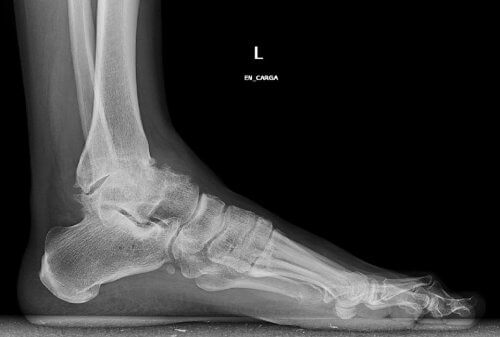

Denne typen artrose er forårsaket av progressiv slitasje på brusken i ankelleddet. Det er vanlig at våre ankler blir stive og utvikler deformiteter etterhvert som vi blir eldre.

- Eksperter opplyser også denne merkelige årsaken til tilstanden: misdannelse av selve ankelen. Noen ganger har vi større sannsynlighet for å utvikle artrose over tid bare ved å ha flate føtter.